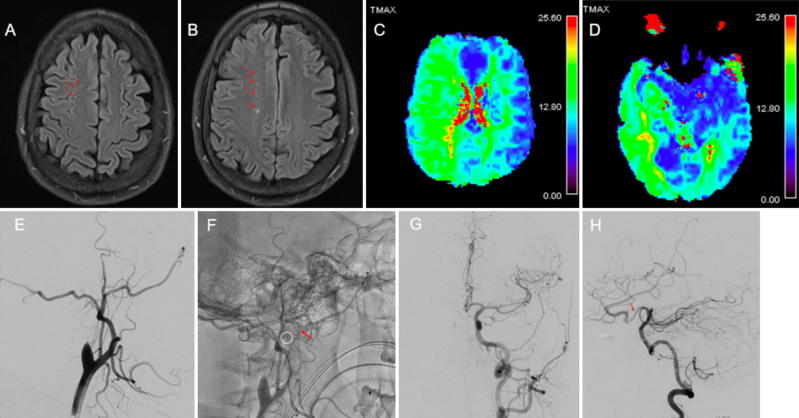

Observations: A 38-year-old male with OI type I presented with a symptomatic left internal carotid artery (ICA) occlusive dissection managed with endovascular revascularization and stenting. Follow-up surveillance imaging identified an incidental right ICA dissection, also treated with stenting. Four years later, the patient experienced new right hemispheric symptoms. He was found to have progressive right ICA dissection on best medical management. Following an unsuccessful restenting attempt, he underwent a successful double-barrel superficial temporal artery-to-middle cerebral artery (STA-MCA) bypass to restore cerebral perfusion with no perioperative complications. Six-month follow-up DSA confirmed a patent bypass with robust flow, and the patient remained asymptomatic 1 year postoperatively.